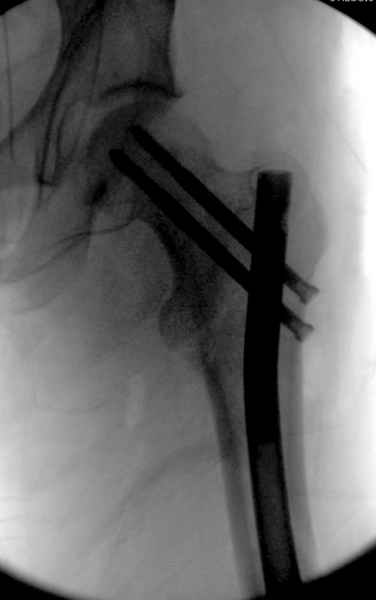

Как раз недавно у меня был примерный случай: больному 36 лет, поступил ночью, травма в результате мотоциклетной аварии, кроме чрезвертельного и спирального перелома левого бедра имеется переломы костей предплечья с этой же стороны. Скелетное вытяжение, а на следующий день больной про оперирован на ортопедическом столе с дистракцией. Чтобы не расколоть чрезвертельный перелом провели временную спицу ближе к переднему кортексу, из малого разреза костодержатель для репозиции, а фиксацию провели антиградным штифтом. Этапы операции на снимках.

Да, сейчас это и у нас самый напрашивающийся выбор. Сделали гвоздем ChM, картинки в приложении.